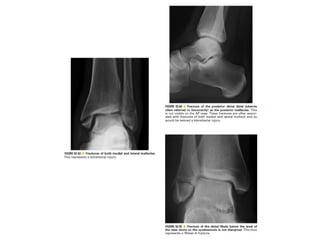

Skeletal trauma was presented by Dr Laith Fadhel with reference to Grainger's Diagnostic Radiology textbook. The presentation covered skeletal trauma as assessed through diagnostic radiology techniques. Key findings and treatments for skeletal injuries were likely discussed.